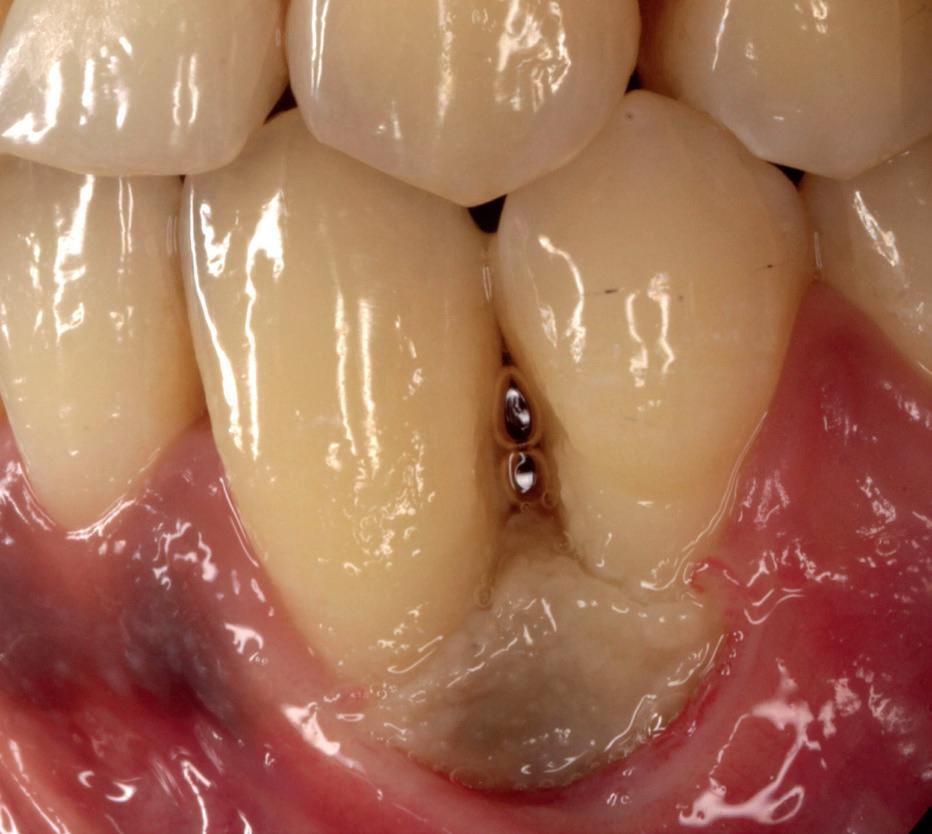

Zes maanden na extractie wordt het implantaat 37 geplaatst. Er is sprake van een goede genezing en de processushoogte en -breedte zijn behouden en opgebouwd. Ook is er zichtbaar gekeratiniseerd weefsel

1 2 Ridge preservation met d-PTFE membranen 35

gewonnen. De wond kan na het plaatsen van een healing abutment primair gesloten worden (Afbeelding 3a-3d).

In afbeeldingen 4a-c is het resultaat drie maanden na het plaatsen van het implantaat te zien. De genezing is volledig en de verwijzer kan de suprastructuur vervaardigen (afbeelding 4a-4c).